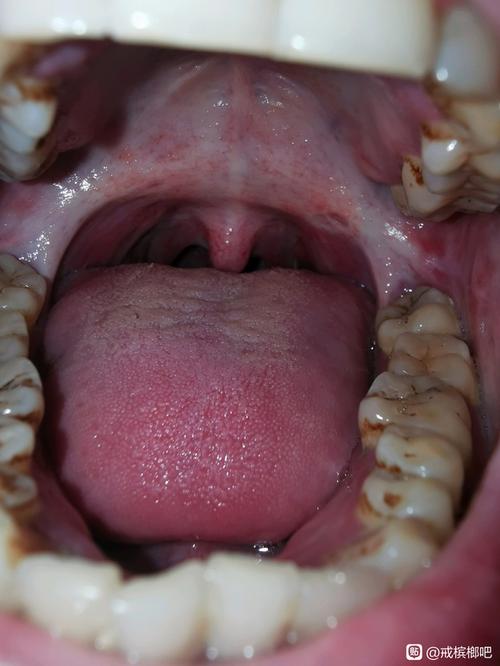

口腔黏膜下纤维化是一种慢性、隐匿性、具有癌变风险的疾病,其本质是口腔黏膜和深层结缔组织因慢性刺激(主要是咀嚼槟榔)而发生的胶原纤维过度增生与变性,导致组织失去弹性、变硬,最终引起张口受限和吞咽困难。

晚期意味着疾病已经发展到非常严重的阶段,组织结构和功能都受到了不可逆的损害。

晚期的主要临床表现

晚期的症状会非常显著和痛苦,严重影响患者的生活质量。

张口受限 - 最典型的晚期症状

- 原因: 口腔软组织(包括颊黏膜、唇、舌系带、软腭等)因纤维化而变得像皮革一样坚硬、缺乏弹性,纤维组织挛缩,像“瘢痕”一样将上下颌骨“拉”在一起。

- 患者可能只能张开手指宽度(1-3厘米)的口,甚至完全无法张口。

- 无法正常进食、刷牙、说话,甚至呼吸困难。

- 张口时伴随剧烈疼痛和牵拉感。